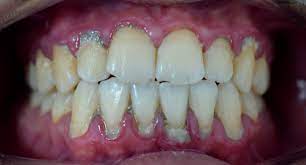

2. 치아 주위 붓기: 치주염이 진행되면 잇몸 주위 조직이 붓게 됩니다. 이로 인해 잇몸이 붓고 부풀어오르며 거의 항상 충혈된 상태를 유지합니다.

4. 치아 이동 및 흔들림: 치주염이 진행되면 치아 주변 조직의 파괴로 인해 치아가 이동하거나 흔들릴 수 있습니다. 이는 치아의 안정성을 잃게 하고 치아의 높은 품질을 손상시킬 수 있습니다.

5. 치주주머니 형성: 치주염은 치주주머니(치주낭)라고 불리는 작은 공간을 형성할 수 있습니다. 이 주머니는 치아와 잇몸 사이에 형성되며 세균이 모이고 번식하기 적합한 환경을 제공합니다.

1. 치아 손실: 치주염은 치아 주변 조직의 파괴를 초래하며, 치주주머니의 깊이가 증가할수록 치아를 지지하는 뼈가 손상될 수 있습니다. 이로 인해 치아가 이동하거나 흔들릴 수 있으며, 치아 손실의 주요 원인 중 하나가 됩니다.

2. 뼈 손상: 치주염은 치아 주변 뼈에 손상을 일으킬 수 있으며, 이로 인해 뼈의 감소와 조직의 파괴가 발생할 수 있습니다. 심한 경우, 이로 인해 치아를 잃는 결과로 이어질 수 있습니다.